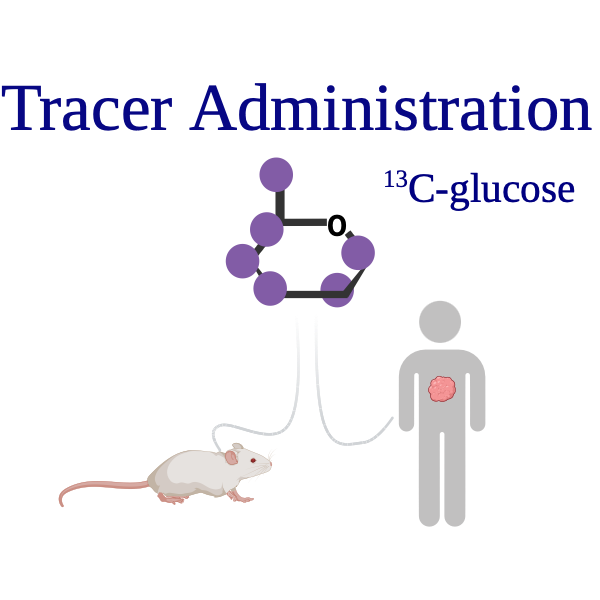

How Stable Isotope Tracing Works

Step (1)

Administer stable isotope-labeled nutrients (e.g., 13C-glucose, 15N-glutamine)